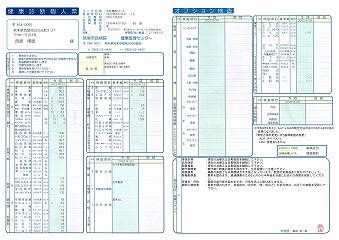

0140 健康診断結果

0109 24.7.29健康診断=pdf

0108 ①22.8.23荒尾市民病院=pdf ②2023-08-21健康診断結果.pdf 8/10(木)受診 荒尾市民病院

2024.18.14 荒尾市民病院 2023.08.10 荒尾市民病院

2024 PDF 2023 PDF